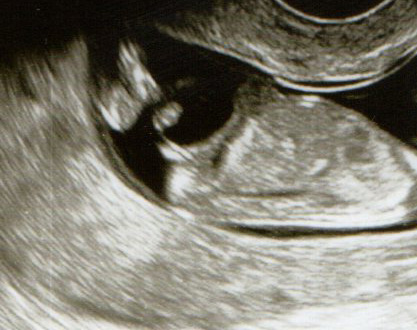

I wondered if you could all take a look at my nub pictures from 12+1. All but one of them seem to look flat and the one that is sticking up a little bit doesn't seem to be a very good pic at all? Thanking you all in advance!

Attachment 12792Attachment 12790Attachment 12791Attachment 12793